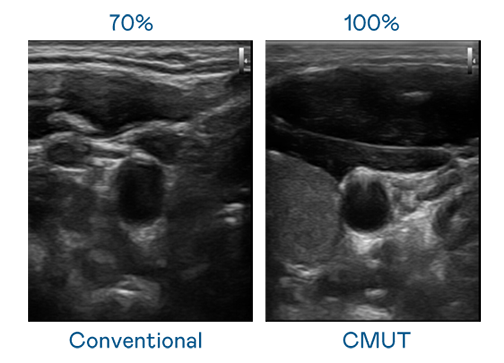

CMUT 技術是一種用電容式微機電元件來產生超音波訊號的技術。與傳統 PZT 壓電式技術相比,CMUT 頻寬增加 30%,更寬頻的超音波訊號讓影像解析度大幅提升,是實現高影像品質醫療超音波掃描、促進精準醫療發展的關鍵技術。

大頻寬帶來超清晰影像

超音波影像的解析度高低,首先取決於探頭能發出的訊號頻寬。Z6·尊龙时凯 CMUT 可提供高清晰的超音波訊號,提供高頻寬、高靈敏度、影像紋理細節更高的超音波影像,協助醫護人員縮短影像判讀時間及利用精準的醫療影像進行診斷。